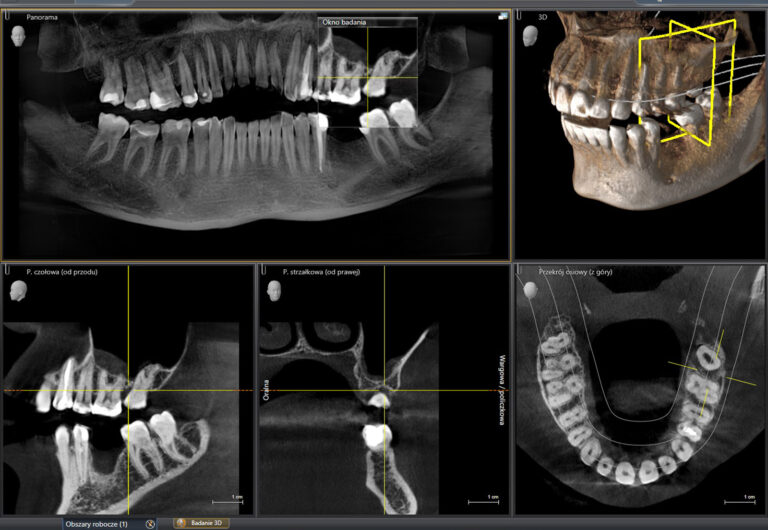

W wielu sytuacjach np. przed leczeniem endodontycznym czy zabiegami chirurgicznymi niezbędne jest wykonanie bardziej szczegółowych badań, do których należy CBCT – cyfrowa tomografia stożkowa kości. Otrzymujemy wtedy obraz 3D badanych struktur.

Tomografia stożkowa CBCT okolicy twarzoczaski lub wybranych struktur głowy,

( w różnych rozmiarach oraz w rozdzielczości do 80um)